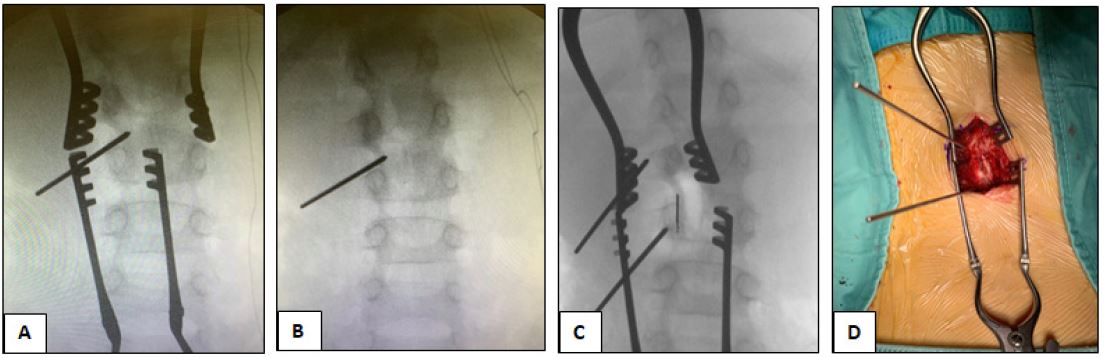

Review of X-Ray of the spine showed a convex right large radius curve (Figure 1). As suspicion was made on bone tumor, MRI scan of the spine was done which revealed a focal alteration of L2 with partial involvement of the left hemi portion of the soma of the entire vertebral peduncle with high signal in the long aTR frequencies. Furthermore, focal alterations of the muscle tissues adjacent to the L2 soma and to the peduncle were also reported (Figure 2).

Among available treatment modalities, we choose the surgical treatment. The parents were given detailed explanations about the procedure. Informed written consent were signed. After a thorough preanesthetic evaluation and adequate fasting period, general anesthesia was induced on the patient with oxygen and Propofol and Laryngeal Mask Airway was inserted for airway management. Anesthesia was maintained with oxygen and inhalation anesthesia with adequate dose of Fentanyl and analgesic. The patient was positioned prone and skin preparation and draping were done as standard protocol. A L2-L3 epispinous incision of approximately 5 cm was made. Dieresis of the subcutis, adequate hemostasis to avoid excessive bleeding and subsequent fasciotomy was practiced. A subperiosteal exposure of the L2-L3 level on the left was performed. The lesion was localized with the help of fluoroscopic assistance to confirm accurate position. A left hemilaminectomy was performed. A high-speed burr was used to break through the cortex overlying the nidus, it was removed using the curettes and the tumor bed was cleaned with a high-speed burr (Figure 3). After the procedure an accurate anatomical plane suture and a sterile dressing was performed. Total duration of procedure was about 2 hours. Recovery of the child from anesthesia was uneventful. The next day the pain score was assessed to be “zero on ten” at rest and “three on ten” while sitting up and in an orthostatic position.

In fact, we observed that before the surgery the Cobb angle was 12.8° Cobb and 12 months after, it was 7.8° Cobb.

Figure 1: (A) Preoperative X-ray showing right convex scoliosis. (B) 1-year FU X-ray showing reduction of the scoliosis.

Figure 3: (A,B) Intraoperative X-ray with landmark before OO excision. (C) Intraoperative X-ray with landmark after OO excision. (D) Intraoperative picture showing K-wires used as landmark.